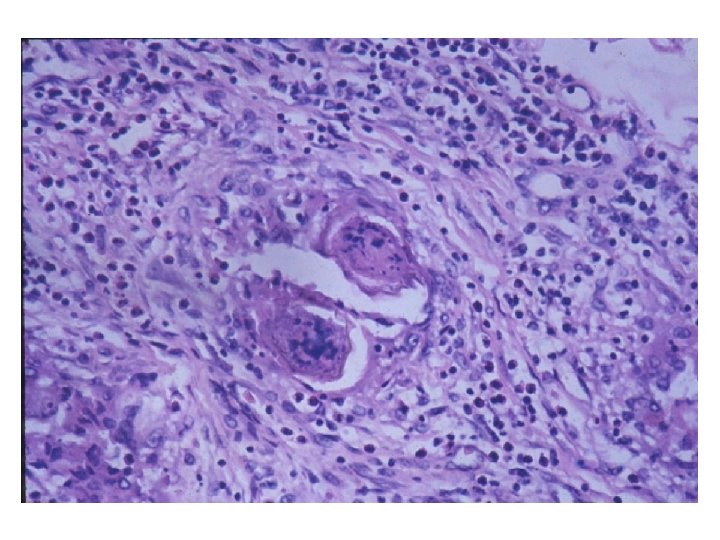

IMUNIDADE A BACTÉRIAS INTRACELULARES Imunidade resultando em cura Mycobacterium tuberculosis Rx de tórax mostrando calcificação no hilo pulmonar esquerdo após cura da tuberculose primária Alteração da resposta imune resultando em lesão Mycobacterium leprae pólo tuberculóide pólo lepromatoso M. tuberculosis Granuloma pulmonar